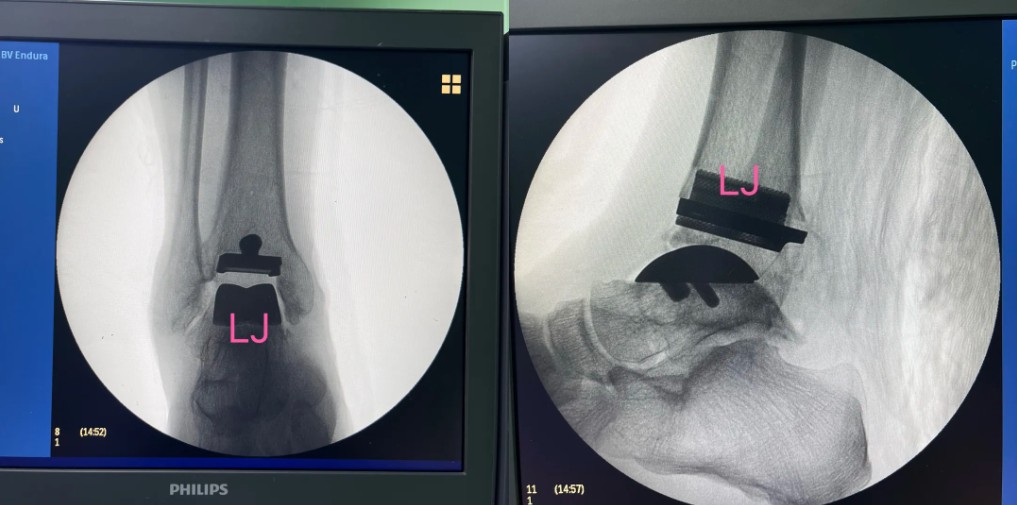

術(shù)后影像